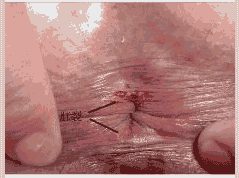

肛裂是以肛门周期性疼痛,即排便时阵发性刀割样疼痛,便后数分钟缓解,主要表现为排便疼痛、出血、便秘。引起肛裂的原因主要有以下4点:

①外伤:干硬粪便或者异物等损伤肛管皮肤,导致肛裂;

②便秘:长期便秘,导致在排便时出现肛门裂开情况;

③感染:肛裂发病时,会逐渐向下蔓延而致皮下脓肿等感染;

④不良的排便习惯:会加重直肠肛门和盆底肌肉的负担,导致肛裂的发生。